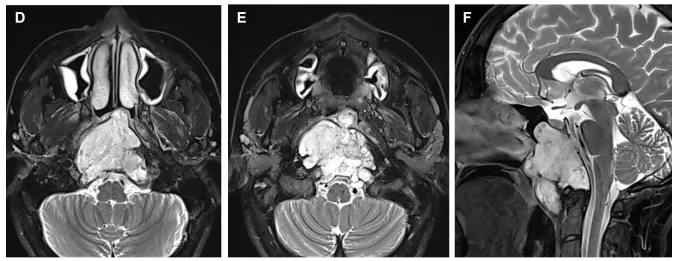

术前术后影像资料对比。术前(红色箭头):图A、B显示了下斜坡及齿状突可见中线占位病变,影像学表现为脊索瘤侧伸有限。术后(蓝色箭头):图C、D显示了用于闭合瘤腔的脂肪移植物,没有肿瘤残留。术后MRI显示完成了肿瘤全切除。术后患者无神经功能缺损。病理检查显示为典型脊索瘤。

术中通过磁共振成像(MRI)监测术后神经功能缺损和术后肿瘤体积。在鼻内镜下以30度和45度角行双鼻孔入路。随后,制作一个心形皮瓣,钻取斜坡以暴露病变(图2)。在初始减压后,轻轻钻取C1环以到达齿状突内及周围的肿瘤,并进行完全切除。

内镜鼻内入路手术技术示意图。(A)显示手术路径(蓝色箭头),以及在鼻咽上部(蓝月牙)形成的心形皮瓣的位置。这张图强调了需要有角度的内窥镜进行更好的术中视野暴露(黄色半透明三角形)(B)为轴向视图,(C)显示了为获得心形皮瓣而进行的切口的术中内窥镜视图,如本例中所用,(D)为冠状视图。(B和D)显示了术后图像分析的结果,在此过程中,Froelich教授对进行骨磨除的部位进行了分段(蓝色),并将其投影到患者的术前CT扫描上。注意,除了下斜坡外,C1环的上部分也被轻微钻孔以到达齿状突的肿瘤。